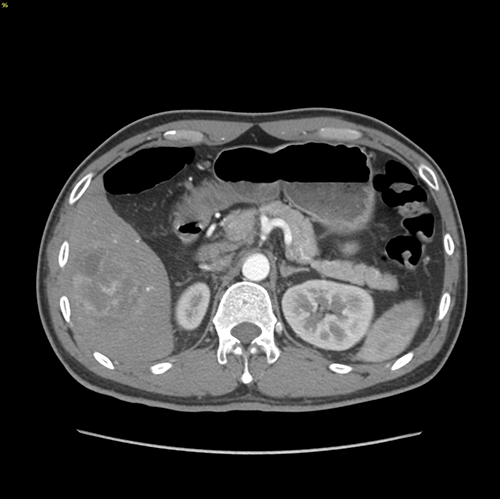

右肝癌-腹腔镜S56肝切除